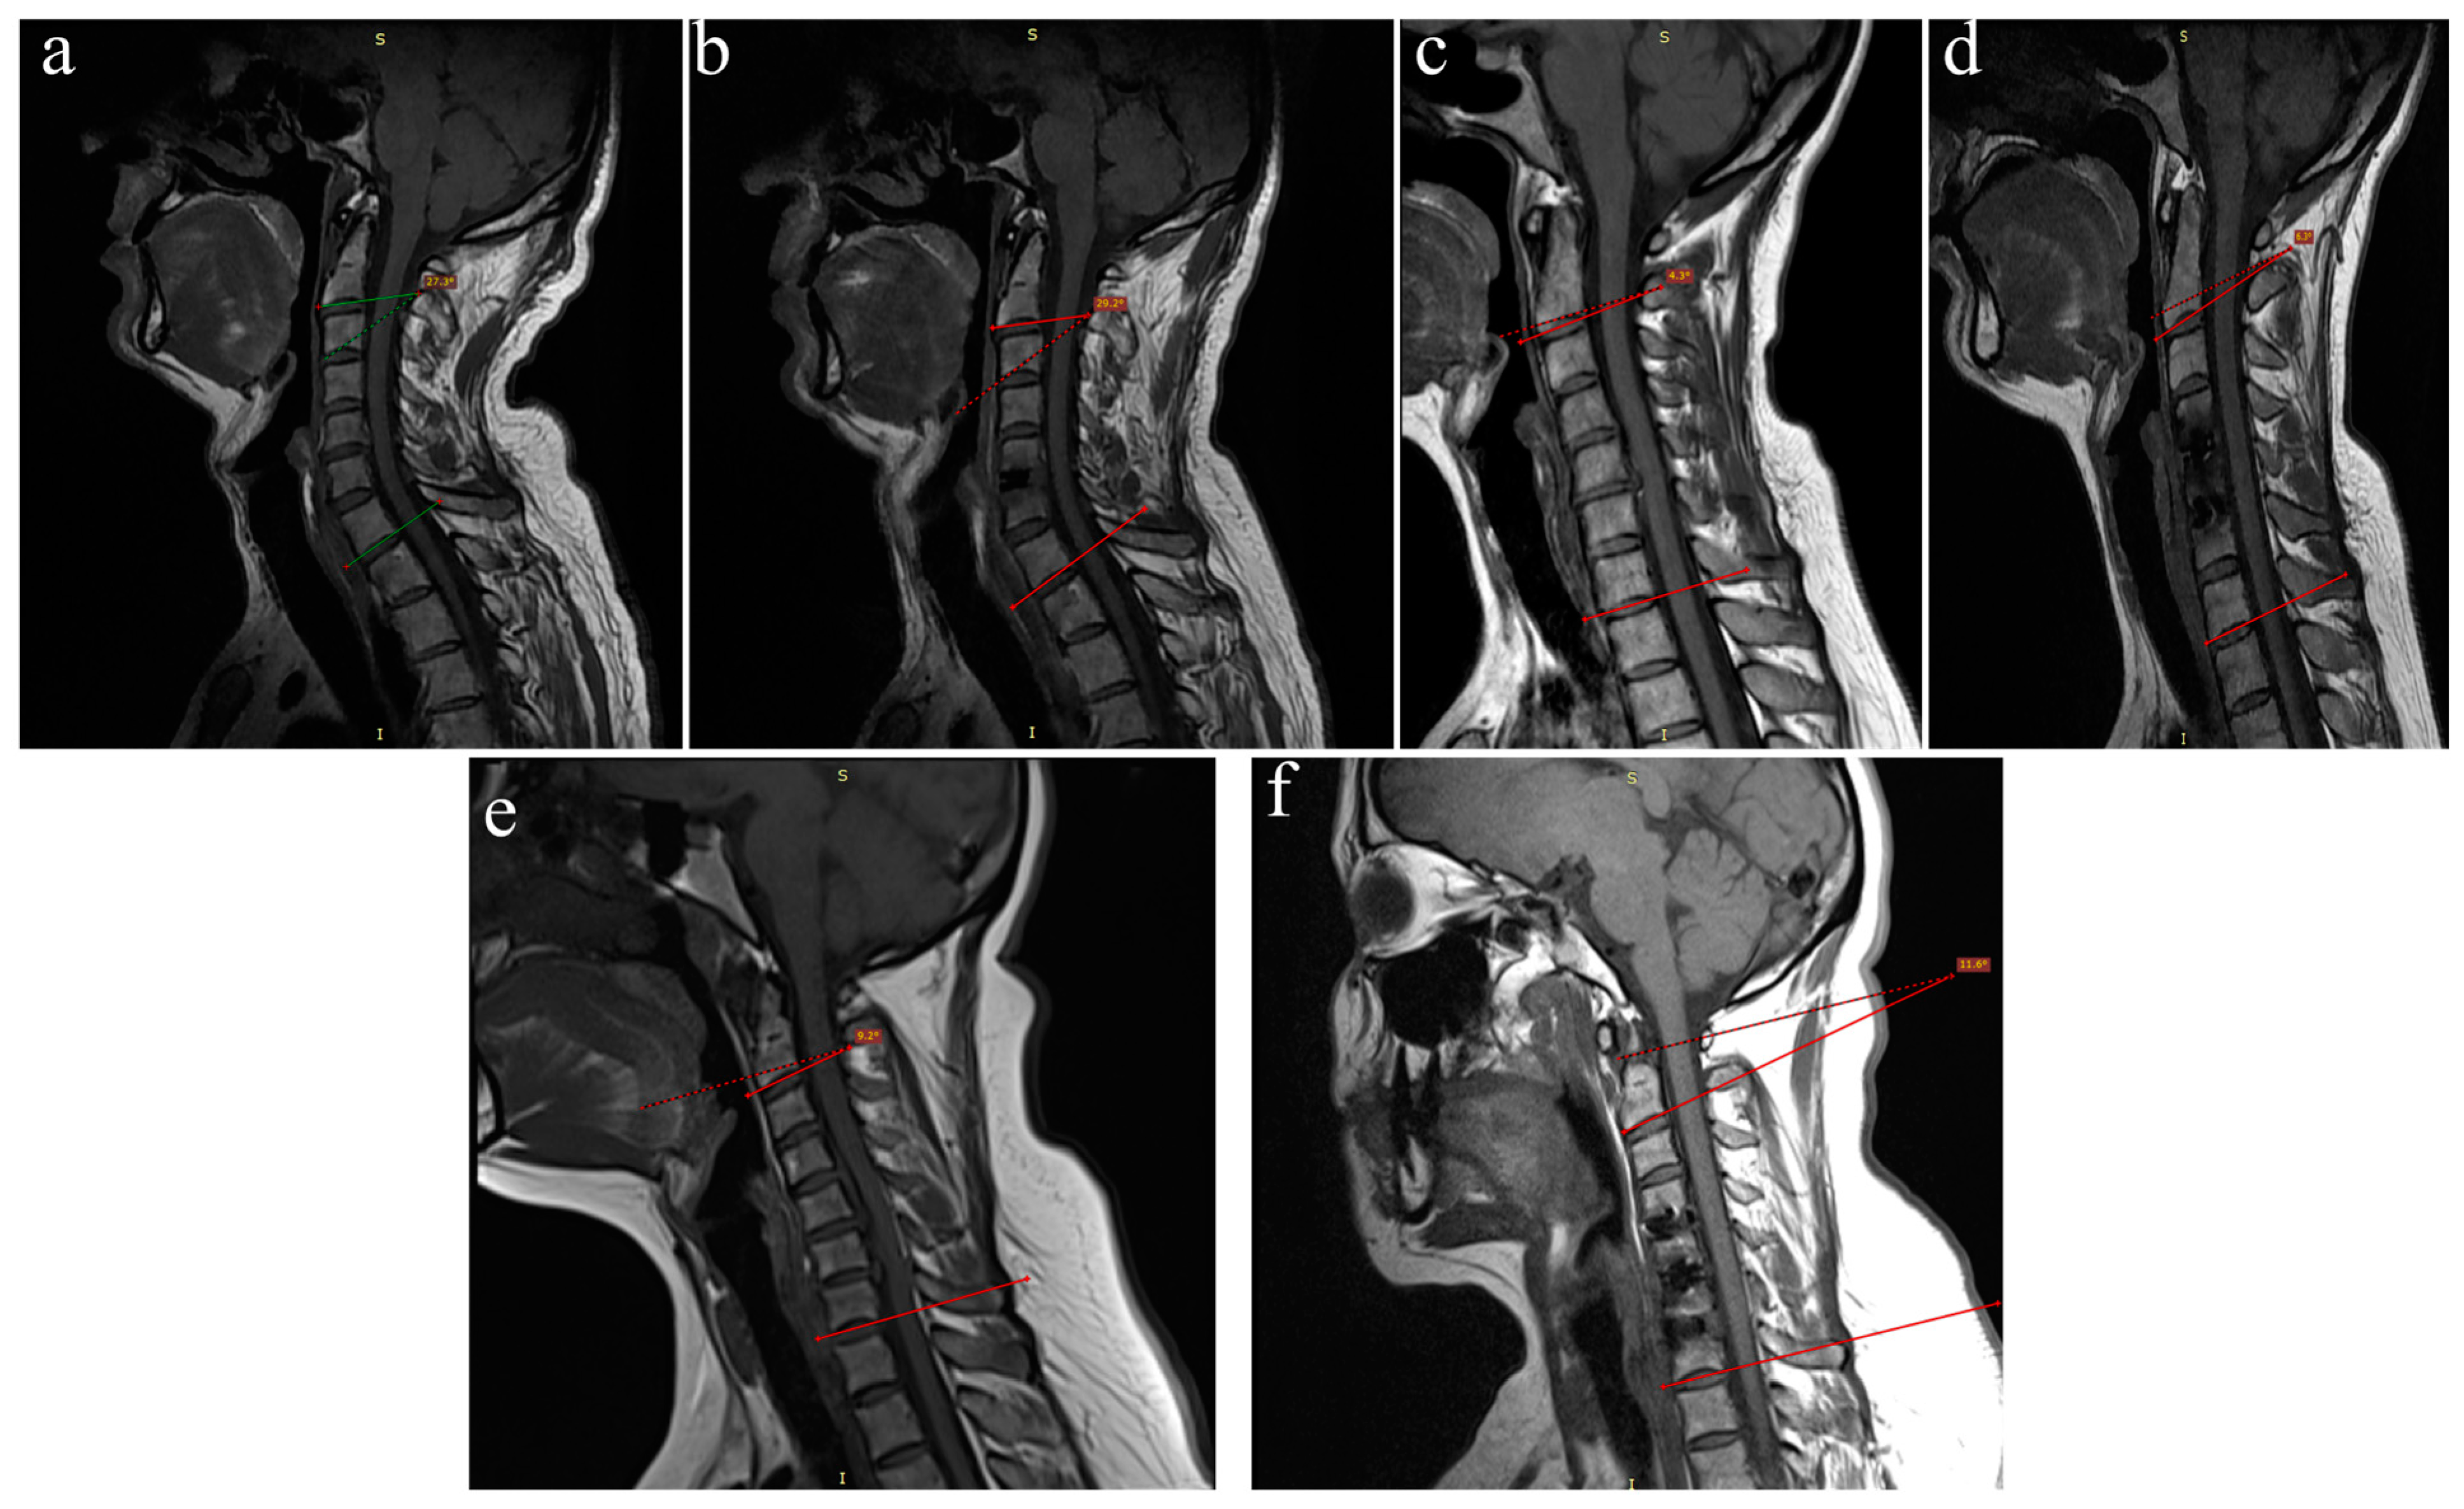

2.2. Radiological Assessment

2.5. Clinical and Radiological Assessment